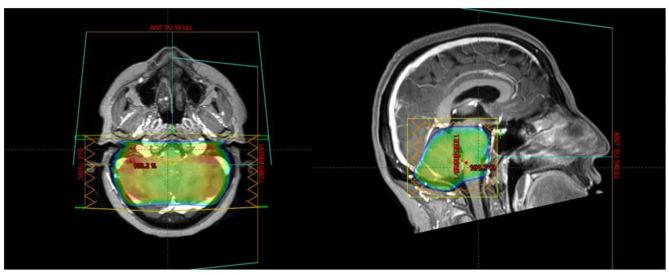

Whole-brain radiotherapy (WBRT) remains a standard treatment for extensive brain metastases, providing symptom relief and improved progression-free survival (PFS). Re-irradiation is often necessary for recurrent disease, particularly in the cerebellum, which accounts for 10-20% of cases. Cerebellar metastases are associated with distinct symptoms and poorer prognoses compared to supratentorial lesions. This study evaluates the outcomes of cerebellar-only re-irradiation for brain metastases, with or without stereotactic radiosurgery (SRS) for supratentorial lesions. A retrospective analysis of 56 patients treated between 2017 and 2023 was conducted. Patients received cerebellar-only re-irradiation after WBRT. Symptom improvement was assessed three months post-treatment. Statistical analyses included t-tests, Mann-Whitney U tests, and multivariable logistic regression. The cohort's median age was 53 years, with breast cancer being the most prevalent histology (71%). Symptom improvement occurred in 75% of patients, with relief rates of 84.6% for nausea, 80% for headache, and 58.3% for dizziness. Dexamethasone use decreased in 76.3% of cases. Median PFS was 39.2%, with a six-month overall survival of 50%. Only 1.7% of patients developed symptomatic radiation necrosis. Factors associated with symptom improvement included younger age, extended intervals between WBRT and re-irradiation, and higher equivalent dose in 2 Gy fractions (EQD2). Cerebellar-only re-irradiation is an effective, low-toxicity option for recurrent cerebellar metastases. This approach warrants further validation in prospective studies, particularly in comparison to SRS.

全脑放疗(WBRT)仍然是广泛脑转移瘤的标准治疗方法,可缓解症状并改善无进展生存期(PFS)。对于复发性疾病,尤其是小脑复发,再次放疗通常是必要的,小脑复发占病例的10%-20%。与幕上病变相比,小脑转移瘤具有独特的症状和较差的预后。本研究评估了仅对小脑进行再次放疗治疗脑转移瘤的疗效,无论幕上病变是否联合立体定向放射外科治疗(SRS)。对2017年至2023年间接受治疗的56例患者进行了回顾性分析。患者在WBRT后仅接受小脑再次放疗。在治疗后三个月评估症状改善情况。统计分析包括t检验、Mann-Whitney U检验和多变量逻辑回归。该队列的中位年龄为53岁,最常见的组织学类型是乳腺癌(71%)。75%的患者症状得到改善,恶心缓解率为84.6%,头痛缓解率为80%,头晕缓解率为58.3%。76.3%的病例地塞米松用量减少。中位PFS为39.2%,六个月总生存率为50%。只有1.7%的患者出现有症状性放射性坏死。与症状改善相关的因素包括年龄较小、WBRT与再次放疗之间的间隔时间延长以及2 Gy分次等效剂量(EQD2)较高。仅对小脑进行再次放疗是复发性小脑转移瘤的一种有效、低毒性的选择。这种方法值得在前瞻性研究中进一步验证,特别是与SRS进行比较。